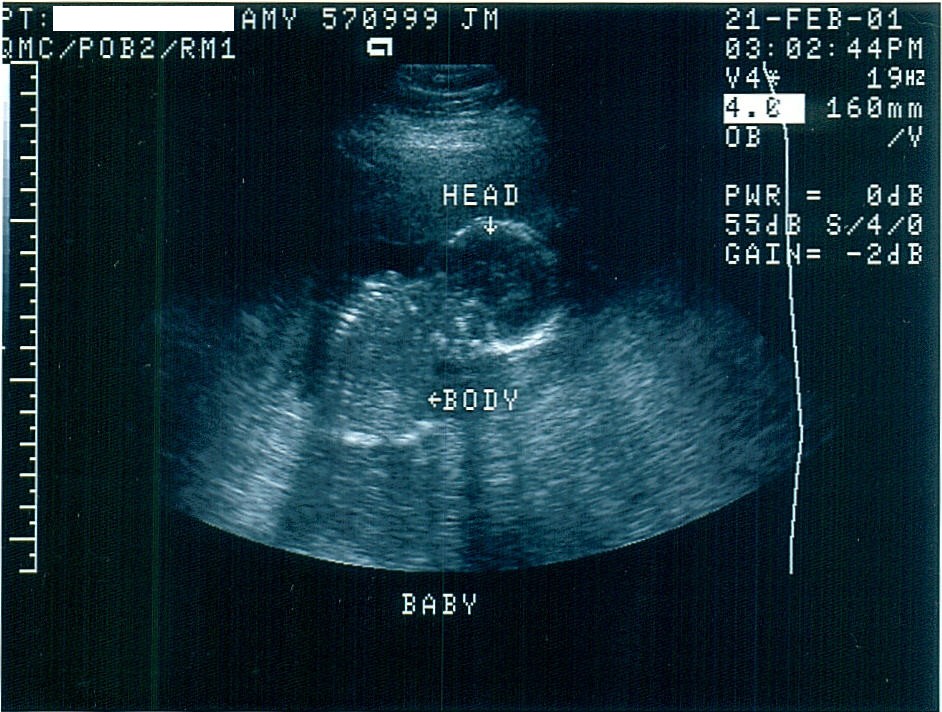

Baby Addie at week 16 -- isn't she beautiful!